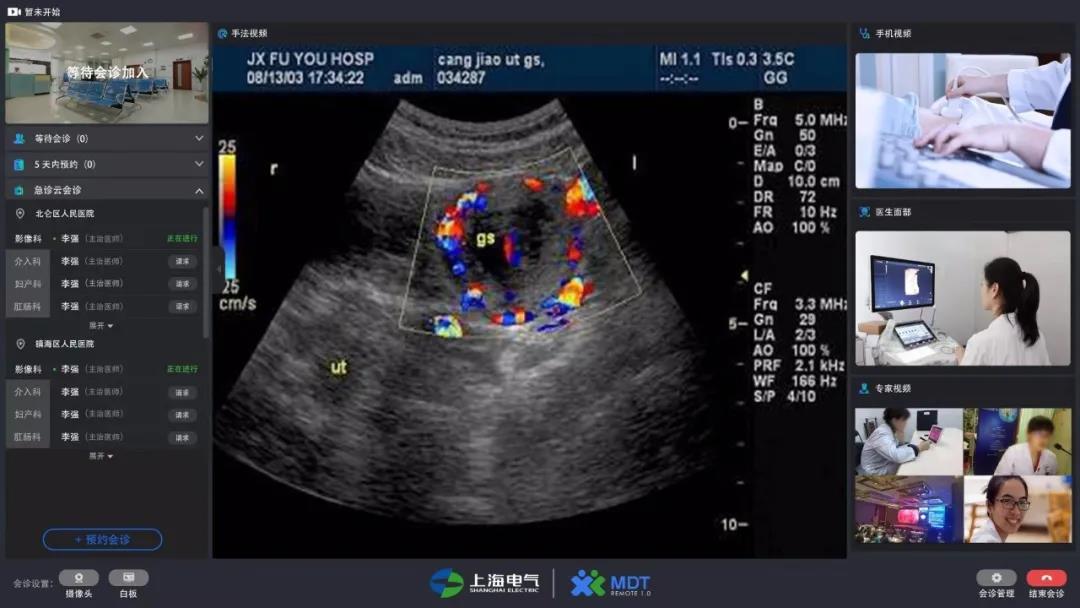

这套名为“MDT1.0多学科远程会诊平台”的5G超声远程会诊系统*基于5G网络技术开发,基本解决了基层医院超声检查*疑难病例的会诊问题。在网络连接正常的情况下,医生只要通过一台电脑、一个摄像头、一个耳麦,就能病人进行实时超声远程会诊*,也免去了医生来回奔波于各个病房的烦劳。

专家通过系统大屏幕既能同步看到动态超声图像*,也能看到操作者操作手法并远程指导操作,实现动态超声影像*与远程医学系统结合,打破传统诊断的局限性。

远程会诊对图像传输要求非常高,需要多路、实时、动态的高清影音图像,这一点在以往传统的网络条件下,超声远程是无法真正达到临床专家的要求的。但在5G条件实测下,系统传输延时不到200毫秒,能确保手法视频、超声视频、医生沟通视频及音频的同步性和一致性。

这个能实现“即插即用”的原因,主要得益于sunbet申搏官方网站自主研发的一款高度集成终端机*:在一体机中嵌入了多路、高清的传输接口,使得整套设备的前端只需要一台显示器大小的一体机,外加一个摄像头,即可启动远程会诊功能*,在行业内是少有的新型解决方案*。